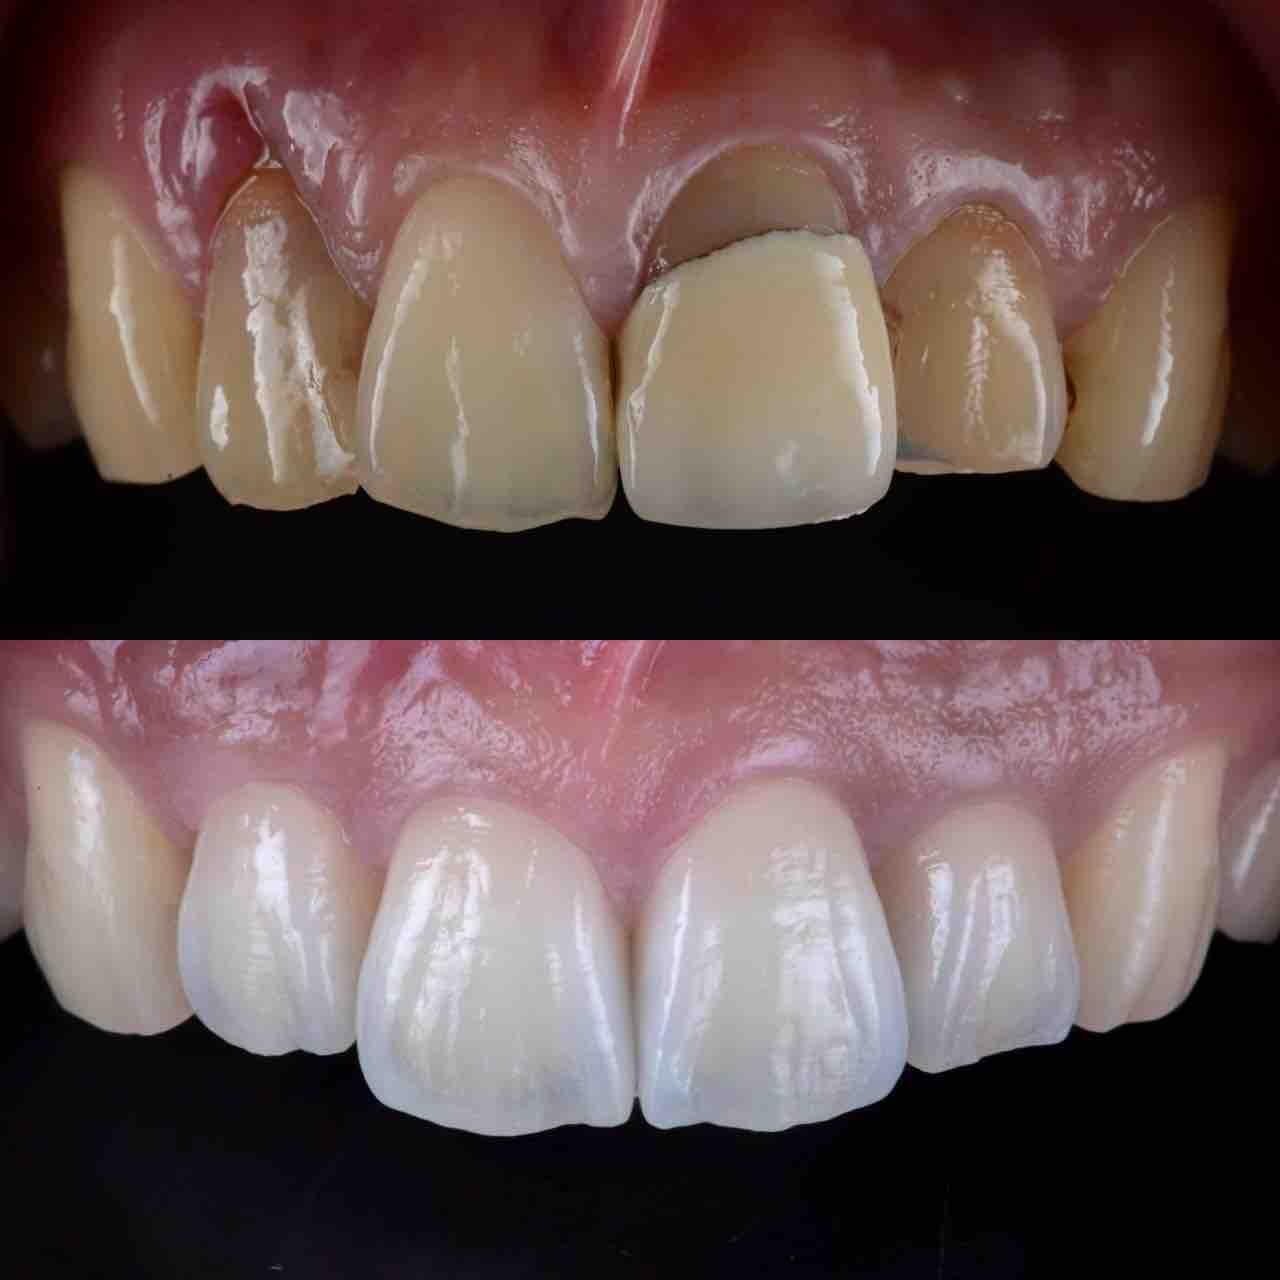

¥¤¥ó¥¹¥¿¥°¥é¥à¤ËºÜ¤»¤Æ¤¤¤ëÅö±¡¤Î¾ÉÎã¤Ç¤¹

ðÌî»õ²Ê¾ÉÎ㢠ÀèÅ··ç»¶ºÀµ¥¤¥ó¥×¥é¥ó¥È

ðÌî»õ²Ê¾ÉÎã¡¶ºÀµ¥¤¥ó¥×¥é¥ó¥È¥»¥é¥ß¥Ã¥¯